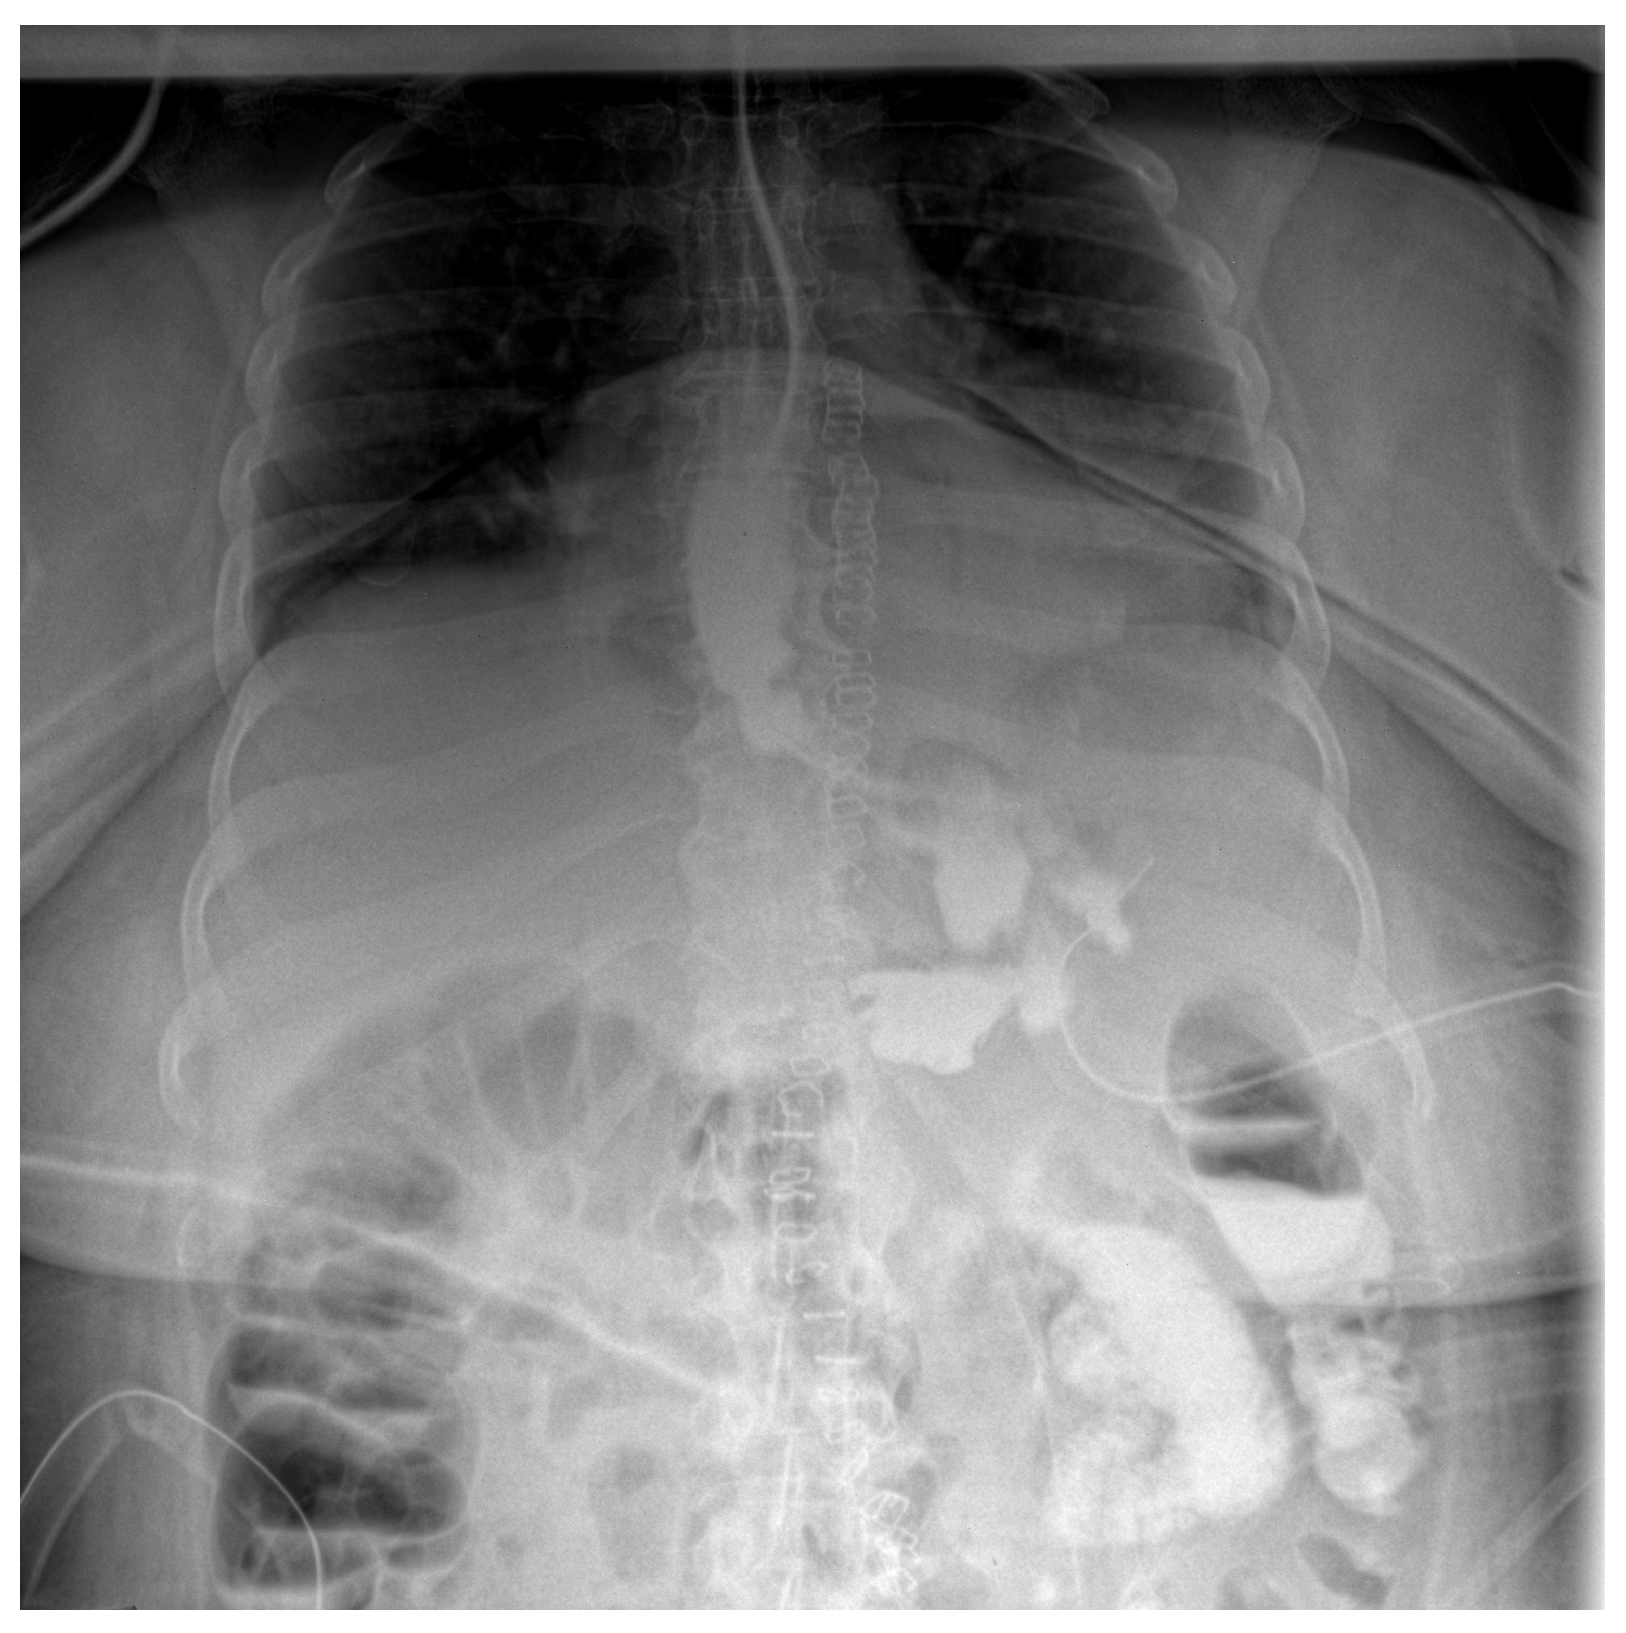

Given the severity of the condition, surgical intervention was deemed necessary; therefore the patient underwent an exploratory laparotomy for definitive therapeutic intervention. The procedure involved the creation of a feeding jejunostomy, peritoneal lavage, placement of two drainage tubes and upper gastrointestinal endoscopy with the insertion of an endoluminal vacuum-assisted closure (E-VAC) system (Figure 2).

Figure 2. Endoscopic aspect of the E-VAC system inserted through the parietal defect.